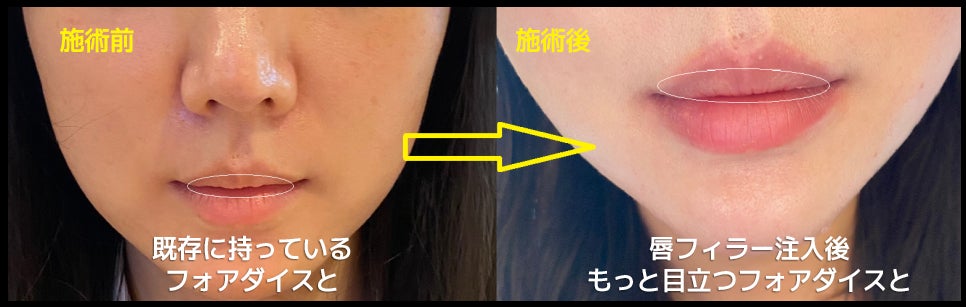

唇のブツブツ:フォアダイスの原因・治し方・予防等について - 美容外科船橋中央クリニック&青山セレスクリニック。

唇のブツブツ:フォアダイスの原因・治し方・予防等について - 美容外科船橋中央クリニック&青山セレスクリニック。

唇のブツブツ:フォアダイスの原因・治し方・予防等について - 美容外科船橋中央クリニック&青山セレスクリニック。

30代男性 唇フォアダイス 電気凝固術- 症例写真 - 美容整形、美容外科なら聖心美容クリニック。

唇のブツブツ:フォアダイスの原因・治し方・予防等について - 美容外科船橋中央クリニック&青山セレスクリニック。